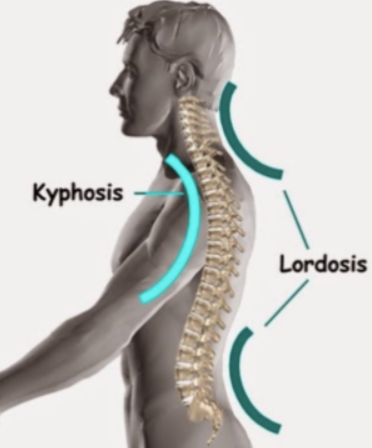

골격의 정렬 이상 또는 뼈의 외상

흉추가 과도하게 굽어있는 굽은등 상태인 후만상태(Excessive thoracic kyphosis)이거나 거북목(Increased cervical lordosis)인 경우에 견갑골문제가 발생할 수 있습니다.

후만과 거북목으로 인해 견갑골이 앞으로 빠지는 전인상태(Scapular protraction)이 되면서 견봉하공간이 좁아지면서 어깨 충돌가능성이 증가할 수 있습니다.

굽은등, 거북목 -> 견갑골 전인상태 -> 견봉하공간 좁아짐 -> 충돌 증가

환자의 경부, 흉부의 해부학적 자세 시 흉추의 Kyphosis, 경추의 거북목, 측만, 견갑골의 대칭성 확인

흉추의 과후만을 교정해주는것이 재활초기에 매우 중요합니다. 여러가지 스트레칭도 중요하지만 평소 바른자세도 지속적으로 시행해주어야합니다.